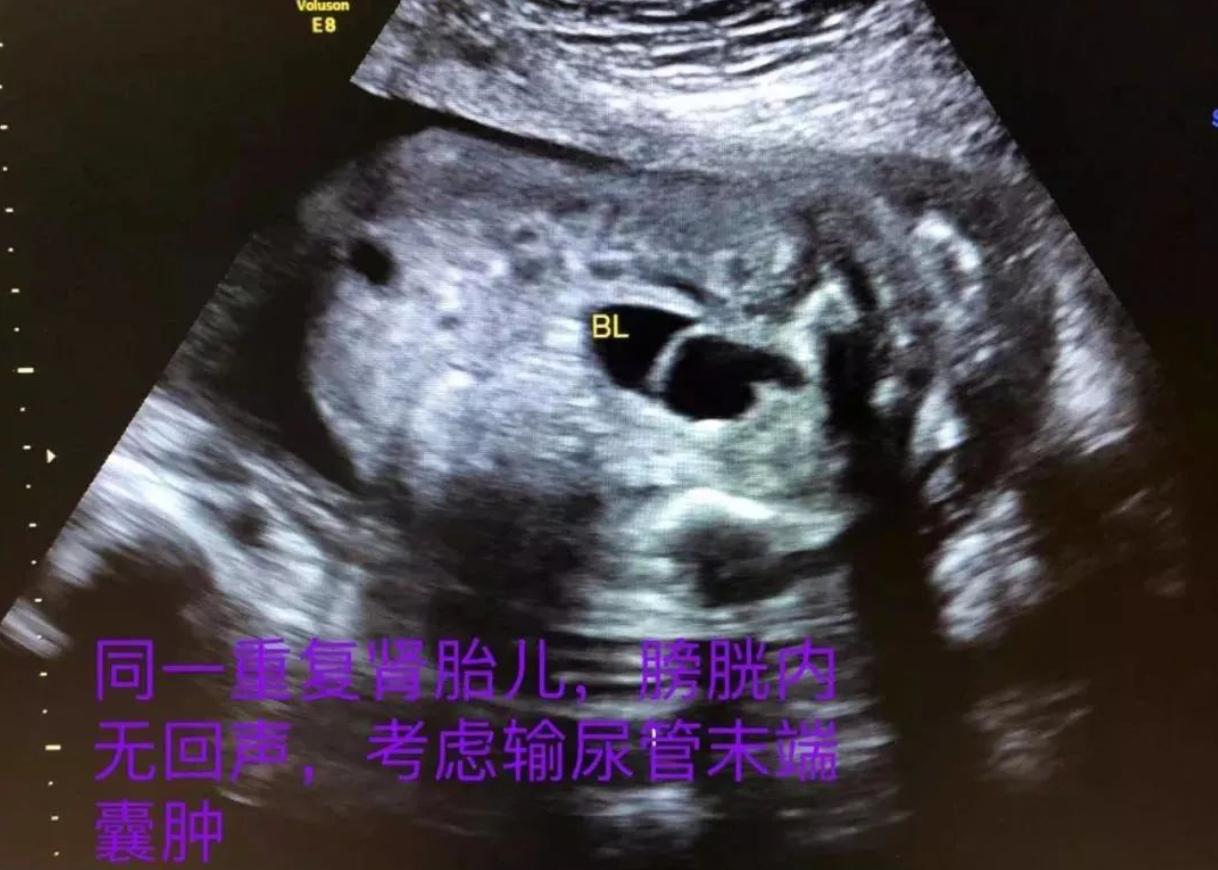

因爲我們做B超的時候,只能看到孩子的心臟有沒有畸形,孩子的五官有沒有畸形?孩子的手有沒有多一個手指或者少一個手指,但是孩子的耳朵聽不聽得到眼睛看不看得到,在B超裏面是沒有辦法去檢測的。